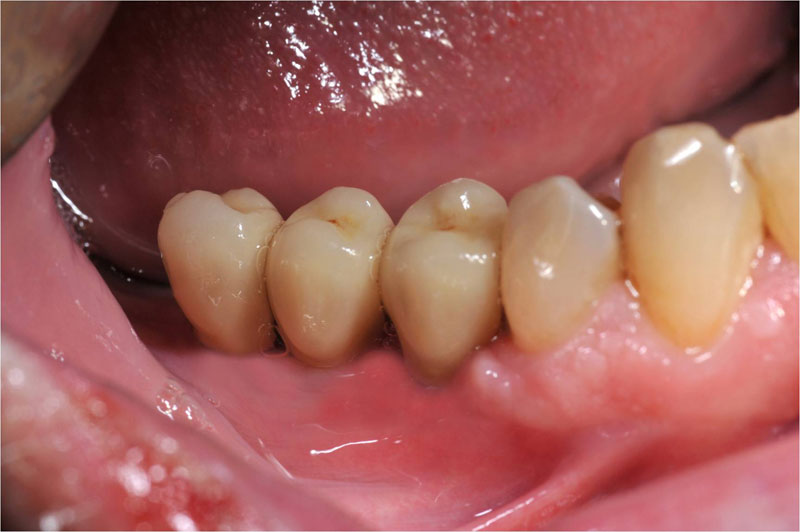

Fehlen in der Front oder im Seitenzahnbereich mehrere Zähne, ist eine Brücke oder Prothese vollkommen unnötig. Die fehlenden Zähne können entweder einzeln durch eine entsprechende Anzahl von Implantaten oder durch implantatgetragene festsitzende Brücken ersetzt werden. Das Bild der Kronen zeigt die drei Verschraubungen deutlich, im Mund liegen diese verdeckt am Gaumen oder im Bereich der Zunge.